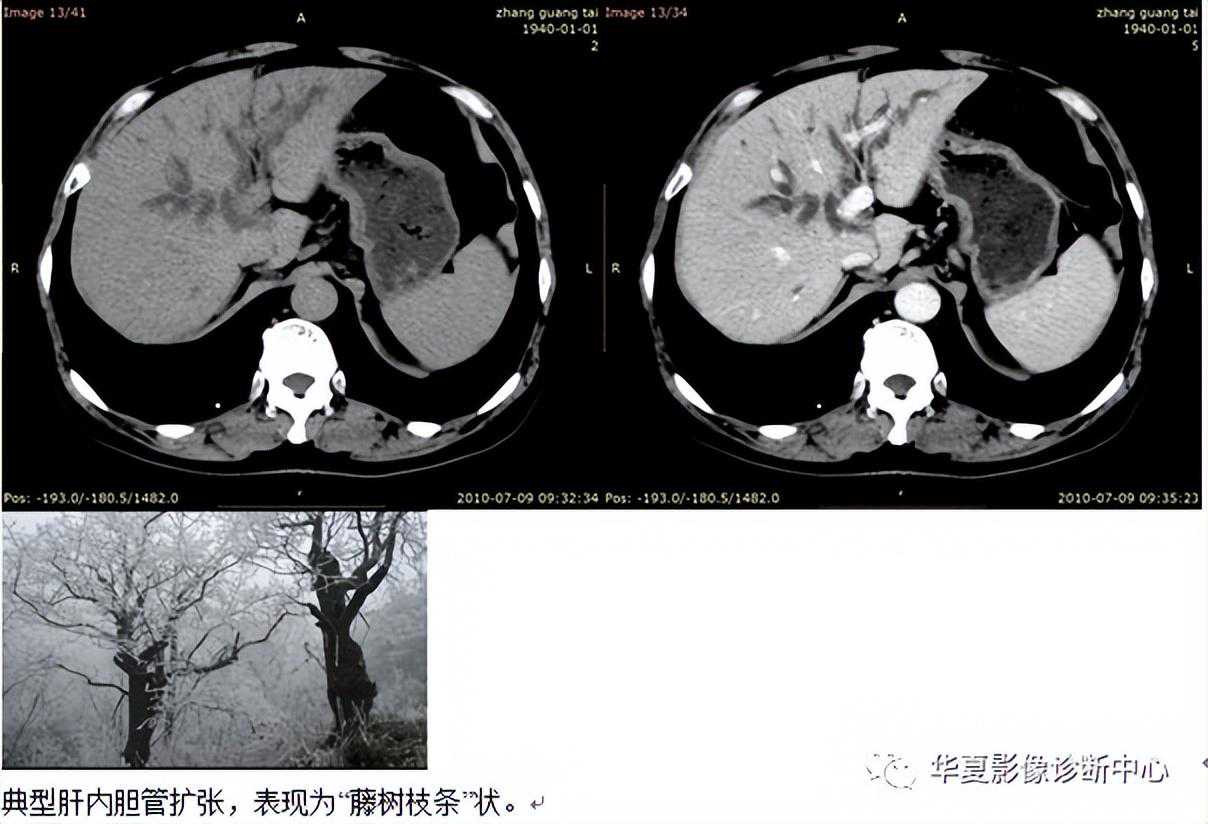

【影像表现】软藤征指肝内胆管扩张。其走行柔和,在CT,MRI,MRCP以及ERCP图像上表现形似藤蔓,故称软藤征。在恶性胆道梗阻中出现率最高。

【征象解释】正常CT,MRI,MRCP以及ERCP图像上,在以肝门为中心的内2/3区域可清晰显示肝内胆管,外1/3区域的胆管一般不显示或显示模糊。当有肿瘤在短期内引起胆管完全梗阻时,由于胆汁淤积,梗阻以上胆管会均匀性重度扩张,可达肝被膜下,因其管壁尚较柔和,故呈软藤状。软藤状胆管扩张提示较急性的梗阻,病因一般以生长较快的肿瘤为多见,如胰腺癌(生长速度较快)、胆管癌等,但其他的病变亦可造成类似的改变。

有无梗阻的诊断:1)PTC和ERCP均可明确显示胆管扩张,前者从病灶头侧显示病变,而后者从病灶足侧观察病变。成功的PTC和ERCP均可显示肝内外胆管扩大,表现从肝门至肝外围由大到小的扩张胆管呈枯枝状或软藤状,胆总管管径)1.1cm,扩大的胆管下端狭窄或阻塞。2)CT显示胆管扩张的准确率达98%~100%;正常肝内胆管一般不能显示,如能显示,其直径仅为1~3mm;当肝内胆管自径达5mm,则认为胆管轻度扩张;达6mm为中度扩张;达8mm以上为重度扩张;表现肝门及肝实质内呈树枝状分布的条状低密度区,形如枯枝状、残根状、软藤状;垂直走向的胆管CT横断面上多呈圆形、类圆形低密度区,增强后无强化;肝总管和胆总管扩张,直径1cm以上,于肝门至胰头之间的CT层面见到圆形或类圆形低密度区,形成自上而下连续不断的环影,环影消失的层面为扩张的胆管末环,提示胆道梗阻的部位口3)II可.见肝内,外胆管管径增大。T1WI呈低信号,T2WI呈高信号;MRCP可见从肝门至肝外围由大到小的高信号扩张胆管,并能从多方位观察扩张胆管下端显示梗阻的部位。

超声和CT则往往要观察分析肝内胆管、胆总管扩张的水平和胆囊、胰管是否扩张以及狭窄、阻塞端的周围解剖来判断胆管梗阻的部位口如出现一侧或两侧肝内胆管扩一张而胆总管正常巨胆囊不扩张,则提示肝门段梗阻;胆总管扩张、胆囊扩张,扩张的胆管末环无胰腺组织包绕,则为胰上段梗限;如果扩张的胆管末环有胰腺组织包绕则说明梗阻位于胰腺段;同时见到胰管扩张,出现所谓的双管征,则梗阻在壶腹段。螺旋CT的MPR重建胆道系统或MRCP,则可得到与PTC相似的图像,且判断梗阻部位更准确。胆道梗阻病因的诊断:常见的胆道梗阻的病因有胆管肿瘤、结石和炎症。前者多为恶性病变,而后两者属良性病变,临床对其间的鉴别非常重要。影像学检杳主要通过观察胆管扩张的形态和程度、梗阻部位、梗阻末端的胆管形态和有无肿瘤转移的征象等进行分析。一般认为扩张的胆管呈枯枝状或残根状,巨扩张较轻多为良性病变;而软藤状中、重度扩张多为恶性肿瘤所致。梗阻部位越高(如肝门部),恶性肿瘤的可能性越大;胰腺段和壶腹段恶性肿瘤和结石都有可能。

恶性梗阻在胰上段及肝门段,多首先考虑胆管癌,其次是淋巴转移,在胰头段多为胰腺痛,在壶腹部多考虑为壶腹癌。恶性征象有:1)软藤征,指肝内胆管扩张,其走行柔和,形似软藤,在恶性胆道梗阻中出现率最高;2)空虚征,最初在ERCP造影中被提出,但也同样适用于ERCP图像,表现为病变以上胆管极度扩张,肝内胆管扩张呈软藤样,病变以下胆管显影止常,而肝门部胆管无显影,致使肝门部胆管充盈缺损呈空虚状态;有约50%的空虚征是由高位胆管癌引起;3)截断征。表现为扩一张的胆管突然变窄或消失,肝门部胆道梗阻时,由于位置较高。肝内胆管树枝状扩张,又称残根征;4)双管征,表现为胆总管及胰管同时扩张,说明梗阻点比较低,多见于胰头癌、壶腹痛及十二指肠乳头癌等;5)软组织肿块影,多数资料认为胆道梗限时,有软组织肿块,同时合并扩张的胆总管突然中断,是诊断恶性胆道梗阻的肯定依据。

软藤征是由于梗阻在较短时间内进行性加重,胆管内压进行性升高,进而导致小胆管腔扩大、小胆管壁变薄所致。此时,胆管壁仍柔软有弹性,阻塞端以上胆管明显扩张、纤曲、延长而呈藕节状。软藤征的出现高度提示着梗阻相应部位恶性肿瘤的存在。软藤征虽然是恶性梗限的一个重要征象,但并不是其特异征象,少数良性梗阻(如医源性胆道损伤、Mirizzi综合征和胆总管结石嵌顿在乳头部等)也可出现软藤征。